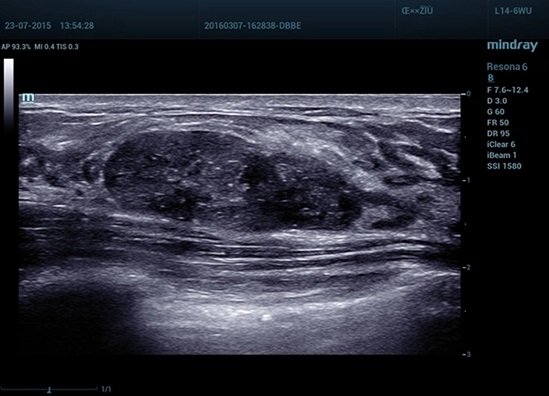

Resona 6 является “упрощенной” версией Resona 7, но при этом обладает всем необходимым функционалом для проведения исследований экспертного уровня. Технология формирования изображения ZST+ и эргономичный монитор с высоким разрешением обеспечивают высококачественную визуализацию.

- ZST+ — программная платформа с технологией зонного сканирования

- HD Scope™ — технология увеличения пространственного разрешения в зоне интереса

HD Scope™ технология увеличения пространственного разрешения в зоне интереса